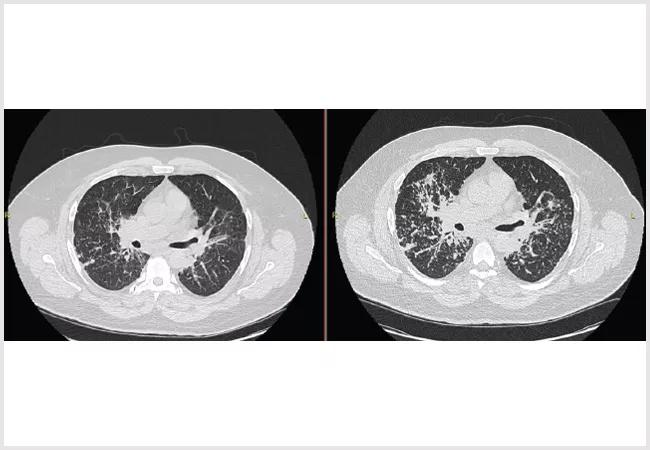

A 54-year-old male originally presented after pre-operative testing for an upcoming orthopedic surgery. The test showed an abnormal CXR prompting further work up with CT chest and subsequent bronchoscopy. A lymph node biopsy demonstrated granulomas consistent with a diagnosis of sarcoidosis.

He was referred to the Cleveland Clinic for sarcoidosis. At the initial visit, he had normal spirometry without obstruction, forced vital capacity of 88% and DLCO of 102% and was asymptomatic. He was followed serially for a year until developing shortness of breath. Repeat imaging demonstrated progressive interstitial disease, and repeat pulmonary function testing showed new moderate obstruction and a drop in FVC to 79% predicted.

The patient was started on steroids and methotrexate. Steroids were weaned off after three months, and methotrexate was titrated to the appropriate dose over several months. After one year of therapy, his CT demonstrated significant improvement, and pulmonary function testing demonstrated resolution of his obstruction and a FVC of 95% predicted. In addition, his symptoms had resolved.